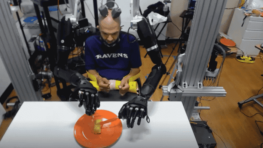

Cet homme tétraplégique mange en utilisant des bras robotisés contrôlés par son cerveau

Cet homme tétraplégique réussit à contrôler des bras robotisés avec son cerveau suite à une opération dans le cadre d’un…

Cet homme tétraplégique réussit à contrôler des bras robotisés avec son cerveau suite à une opération dans le cadre d’un…